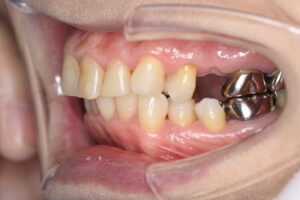

患者様は、奥歯4本の銀歯の色を変えたくて来院されました。虫歯の再発予防もしたいのでセラミックでの治療を希望されており、メリットデメリットと、起こりうるリスクについて説明の後、治療を開始しました。

さらに、金属アレルギーの心配がなく、歯ぐきの黒ずみ(メタルタトゥー)も解消されるため、健康で明るい口元を長期的に維持することが可能になります。

| 銀歯を除去し、ジルコニアブリッジにて補綴処置を行なった。 |

プラークが付きにくい(清潔) セラミック表面はなめらかで、細菌の付着が少なく虫歯や歯周病の再発リスクが低い。 自然な見た目 変色しにくい 金属アレルギーの心配がない 精度が高い |